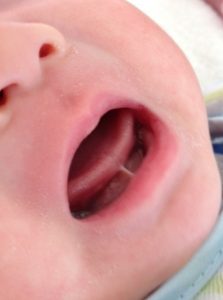

小帯は舌の裏側にある筋で、下顎と舌を繋げています。舌小帯が生まれつき短い状態を一般的に舌小帯短縮症といいますが、舌強直症、舌小帯癒着症、舌癒着症などと呼ばれる事もあります。

舌小帯の程度を簡単に見分ける方法としては、口を大きく開けて舌を上顎につけてみます。縦の大きさの1/2以上舌を上げる事が出来れば症状は軽度です。軽度な場合は日常生活において殆ど問題もなく、舌を上顎や口の横につける事も自由に出来ます。

中等度では舌を上げられるのが1/2以下になります。舌を前に出すとハート型になり、舌先を上顎につけようとしてもなかなかつきません。

重度になると、下顎の歯よりも舌が上に上がらない、もしくは全く上がらない状態となります。舌を前に出そうとしても、下唇までやっと出せるかどうかで、舌を上に上げることも出来ません。